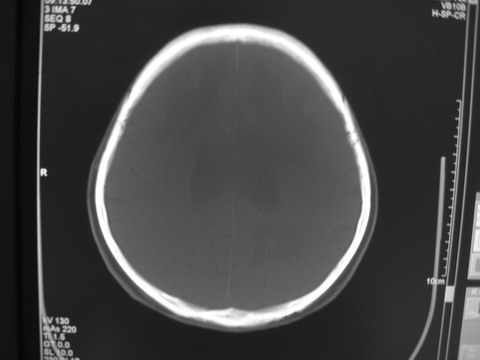

患者 男 69岁 头晕头痛不适

多发病灶,指状水肿,首先诊断转移瘤。

多个结节并周围大面积水肿区,多考虑多发性脑转移瘤

小病灶、大水肿,病灶多发,首先考虑多发转移瘤;建议查原发灶。

额顶叶多发小病灶、大水肿,首先考虑多发转移瘤;建议查原发灶

脑内多发病灶,小病灶,大水肿。

典型转移性肿瘤。

应进一步检查,查找原发病灶。

结果 : 该患者结肠癌病史5年 考虑脑转移